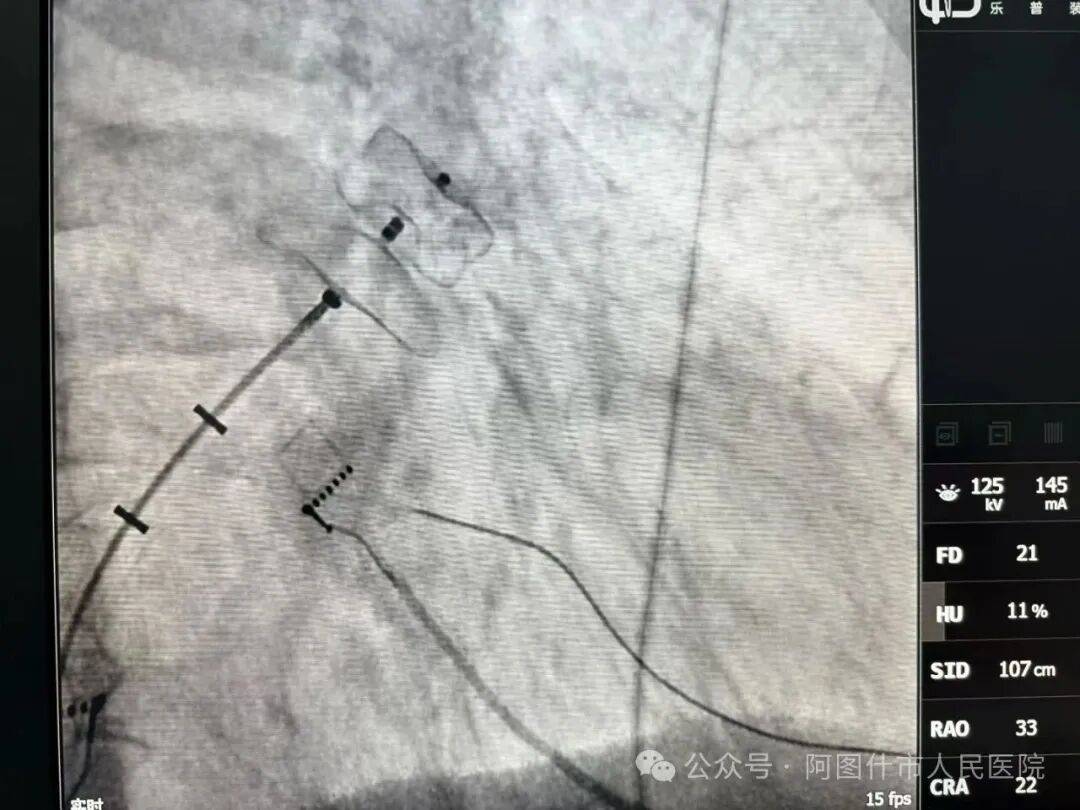

近日,阿图什市人民医院在解放军联勤保障部队第988医院于林君主任、尚冬升主治医师精准示教下,顺利完成5台三维标测引导下的心律失常介入手术,涵盖房颤射频消融+左心耳封堵一站式手术、室上速射频消融术等,精准解决了房颤、室上速患者反复心悸、胸闷、头晕等临床困扰。

据阿图什市人民医院相关负责人介绍,此次开展的三维电标测技术,是当前心律失常消融核心技术,具有定位精准、创伤小、恢复快、疗效确切的显著优势。术前,专家团队带领阿图什市人民医院医护人员反复研讨病例、制定个性化方案;术中,专家亲自主刀完成关键操作,同时示范讲解、手把手带教。最终5台手术均圆满成功,术后患者生命体征平稳、恢复良好。